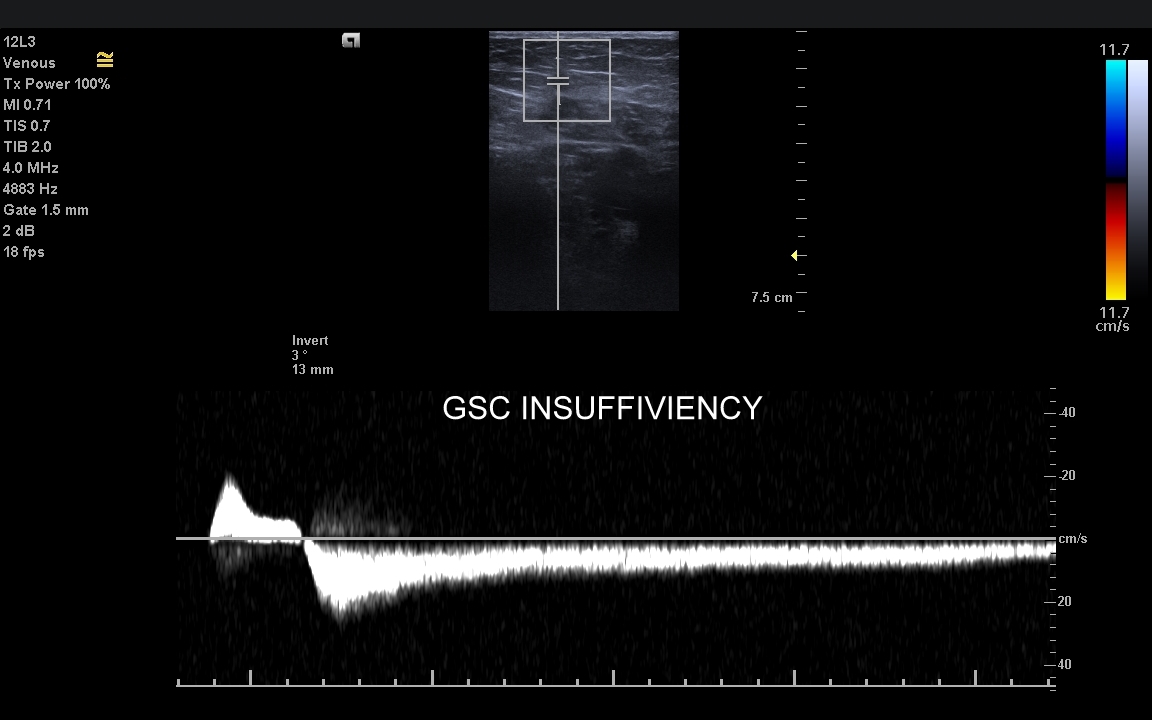

Żyły kończyn dolnych. W obrębie żył kończyn dolnych znajdują się dwa zasadnicze układy żylne – układ żył głębokich i układ żył powierzchownych. Oba układy łączą się razem bezpośrednio w okolicy pachwiny oraz dołu podkolanowego; poza tym na różnych poziomach kończyny przy pomocy żył przeszywających. Każde połączenie układu głębokiego i powierzchownego posiada naturalnie zastawkę, która zapobiega cofaniu się krwi w niewłaściwym kierunku. Prawidłowym kierunkiem jest przepływ z układu powierzchownego do głębokiego oraz ku sercu. Zarówno w układzie powierzchownym, jak i głębokim lokalizować mogą się poważne choroby takie jak zakrzepica, czy niewydolność żylna.

Czym są żylaki? Żylaki to nadmierne i niefizjologiczne poszerzenie odcinka żyły pod wpływem podwyższonego ciśnienia żylnego i zastoju krwi. W poszerzonej żyle dochodzi do zaburzenia, spowolnienia, a nawet odwrócenia kierunku przepływu krwi. Czynniki te sprzyjają wystąpieniu zakrzepicy, a także rozwoju niekorzystnych zmian w strukturze skóry i tkanki podskórnej, które zakończyć się mogą owrzodzeniem kończyny. Zdiagnozowanie przyczyny i źródła żylaków umożliwia zastosowanie celowanego zabiegu chirurgicznego

Badanie USG żył kończyn dolnych najczęściej wykonywane jest w ramach diagnostyki niewydolności żył powierzchownych oraz ich objawów w postaci pajączków żylnych, żylaków kończyn dolnych, obrzęków i owrzodzeń żylnych. Kolejnym pod względem częstości wskazaniem do badania Doppler żył jest podejrzenie zakrzepicy żył głębokich kończyn dolnych, monitorowanie leczenia zakrzepicy oraz ocena jej powikłań odległych. Powikłaniem nieleczonej zakrzepicy żył głębokich może być zespół pozakrzepowy manifestujący się masywnymi obrzękami kończyny i zaburzeniami troficznymi. Badanie USG Doppler żył kończyn dolnych często uzupełniane jest oceną układu żył centralnych w miednicy i jamie brzusznej. W tych obszarach również pojawiać się mogą żylne zmiany zakrzepowe, niedrożności żył, a nawet zmiany nowotworowe.

Podczas najczęściej przeprowadzanego badania, tj. USG Doppler kończyn dolnych, oceniane są żyły głębokie oraz powierzchowne na całej długości kończyny – od stóp aż do pachwiny. Czasami mogą zaistnieć wskazania do rozszerzenia badania na wyższy poziom układu żylnego, tj. na żyły biodrowe w miednicy i żyłę główną dolną w jamie brzusznej. Badanie USG żył jest badaniem dynamicznym, tzn. oprócz oceny wyglądu żył wykonuje się różnorodne próby czynnościowe, takie jak kompresja, głębokie oddychanie, próba Valsavy, podczas których rejestruje się przepływy krwi w żyłach.

W przypadku oceny wydolności żył oraz kwalifikacji Pacjenta do zabiegu na żyłach lub na żylakach kończyn dolnych dynamiczne badanie dopplerowskie żył wykonuje się także w pozycji pionowej. Przy opisanych próbach czynnościowych wykorzystuje się specjalne właściwości sprzętu USG, tj. tryby badań dopplerowskich, tryby duplex i triplex, a także angografię sonograficzną dostępną w aparatach wysokiej klasy.

Czy USG Doppler wykrywa przyczynę żylaków? Zdecydowanie tak. Przyczyną żylaków kończyn dolnych najczęściej jest niewydolność żył powierzchownych na poziomie uda, ale żylaki wynikać mogą także z istnienia krążenia obocznego powstałego na tle niedrożności żył głębokich lub rzadkich malformacji naczyniowych. Uwaga! Przed leczeniem żylaków zawsze należy wykonać szczegółowe badanie USG Doppler!